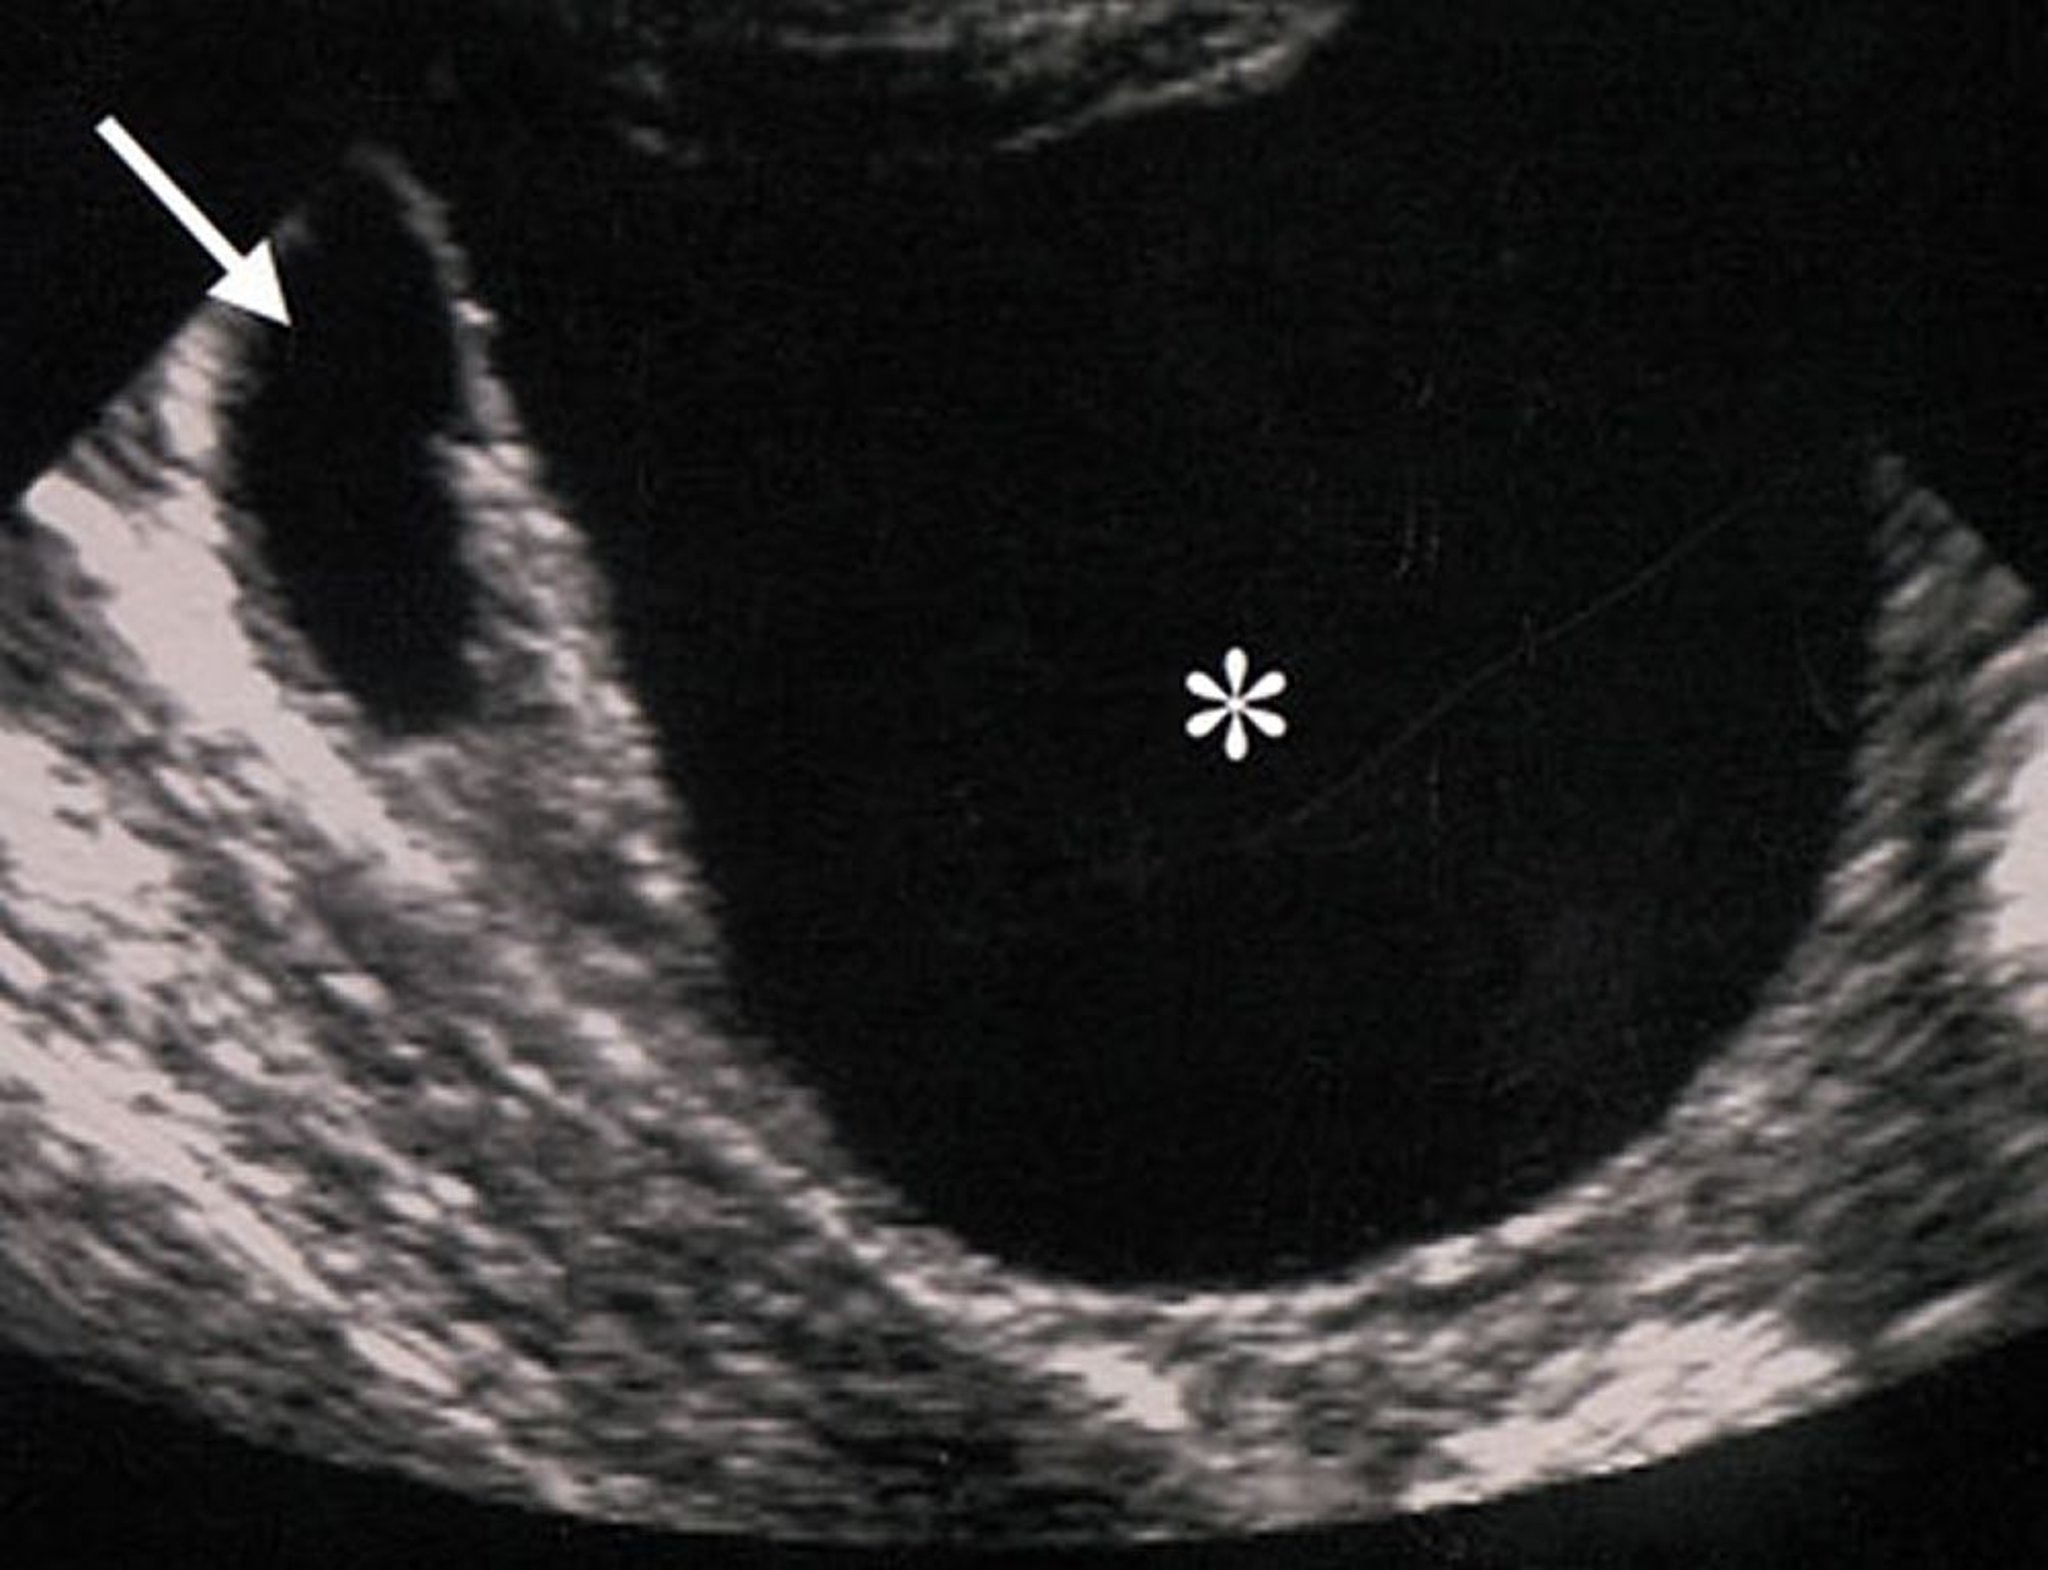

Ecografia di una massa ovarica benigna

Le caratteristiche ecografiche di questa massa ovarica (indicate da un asterisco) suggeriscono che la massa sia benigna. La massa è anecogena (suggerente assenza di componenti solidi), regolare, ben circoscritta e senza ispessimento o escrescenza della parete.